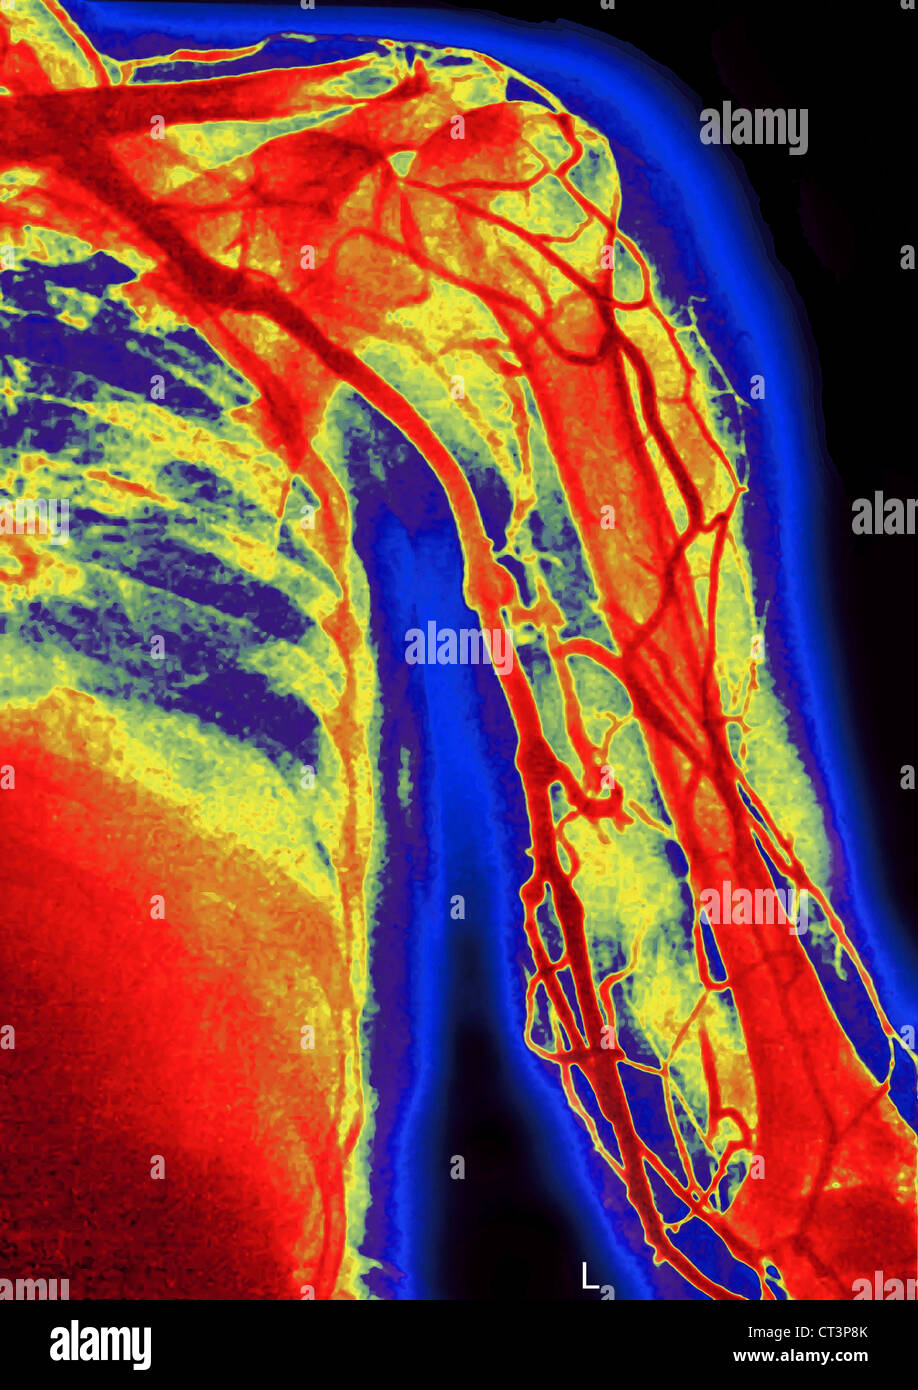

RFEW9HG6–Oberflächlichen Lymphgefäße der oberen Extremität, graviert Vintage Illustration. Üblichen Medizin Wörterbuch - Paul Labarthe - 1885

RFEW91T9–Oberflächlichen Lymphgefäße der oberen Extremität, graviert Vintage Illustration. Üblichen Medizin Wörterbuch - Paul Labarthe - 1885